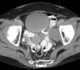

Air hose injury of rectum